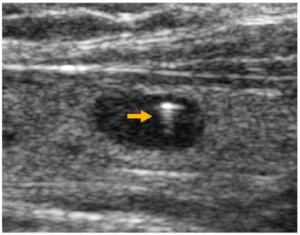

前頸部横走査による甲状腺の超音波像(別冊No. 4)を別に示す。矢印で示すのはどれか。

No. 4